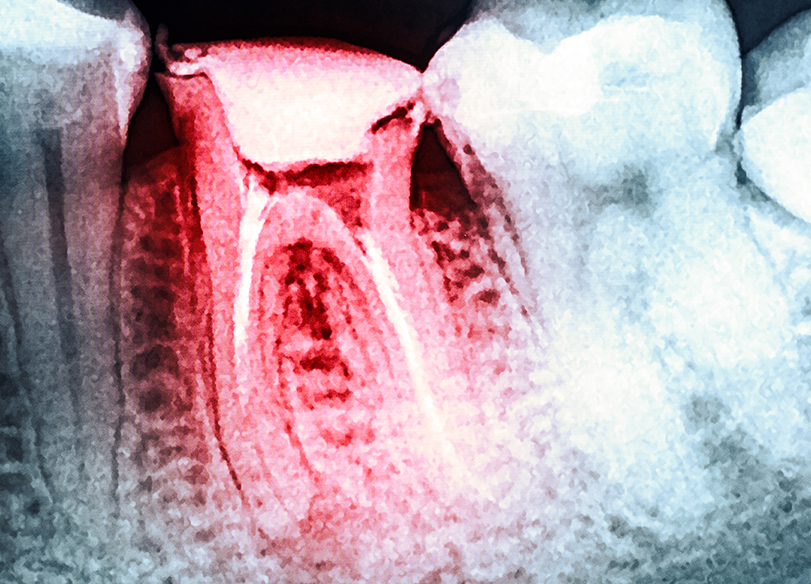

The most important thing to do when you have tooth pain is to seek help from your dentist. When you have a dental appointment, your dentist will make identifying the cause of pain a priority. Using visual examinations and X-rays, your dentist will determine the cause, and then discuss treatment options with you.

If the tooth is infected, and the infection has reached the pulp tissue, the living part of the tooth, antibiotics may be recommended. It may also be advisable to carry out root canal treatment, which involves removing decayed pulp tissue from the root canals and then cleaning and sealing the tooth. A new crown may also be placed.